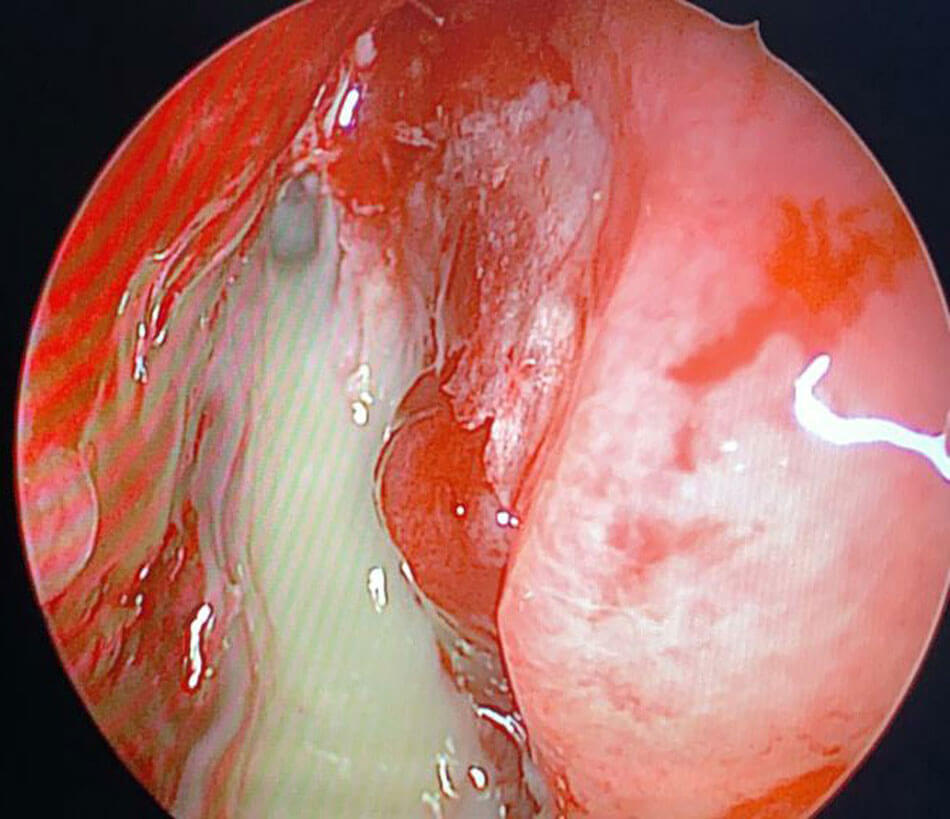

Endoscopic view of pus drained from a frontal lobe abscess through the cribriform plate.

The initial phase saw late presentations including cerebral mucormycosis. But overall, cerebral involvement is about 5-8%. Also, 2-3% of other patients progress to intracranial involvement in spite of aggressive treatment. Cerebritis is managed conservatively with significantly higher doses of amphotericin B. Focal abscesses have been drained by neurosurgeons. About 20% of patients have had some degree of orbital involvement. Surgical management may range from orbital decompression to selective periorbital endoscopic debridement to orbital exenteration (guided by clinical and radiological findings). Most decisions are tailored to the context.